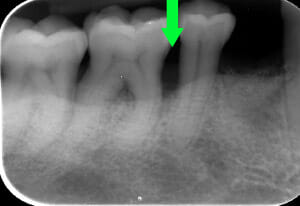

Endorale prima e dopo la cura della parodontite

Con terapia parodontale fotodinamica non chirurgica: si noti la ricrescita naturale dell’osso e del tessuto parodontale.